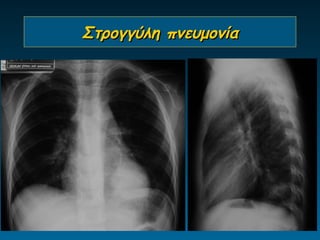

Στρογγύλη πνευμονία